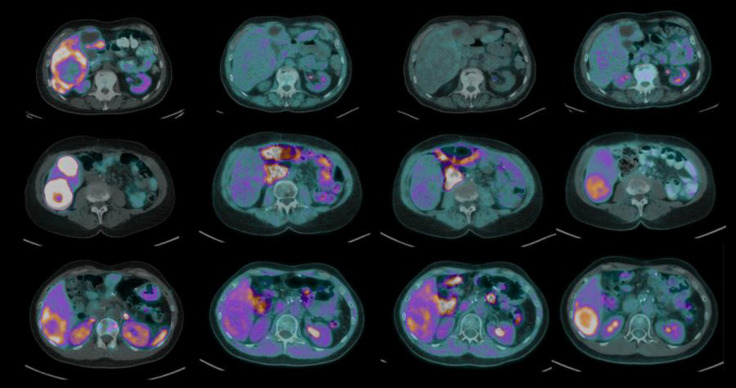

Results: Ten patients were enrolled with primary sites including pancreas (n=3), small bowel (n=3), rectum (n=2), duodenum (n=1) and lung (n=1). Six subjects were scored 1, three subjects were scored 2, and one subject was scored 3. All lesions evaluated were located in the liver. Quantitative [18F]FMISO parametric imaging showed evidence of increased uptake rate (Ki) in the photopenic areas of the DONUT lesions in 8/10 subjects. Surrounding uptake rate in normal liver was extremely low. In the qualitative delayed image assessment, only one subject demonstrated [18F]FMISO uptake greater than surrounding normal liver (small bowel primary, G2).

Conclusion: Only one of ten patients with DONUT lesions demonstrated increased [18F]FMISO uptake rate on delayed static imaging. In contrast, dynamic imaging demonstrated increased [18F]FMISO uptake rate in the region of [68Ga]DOTATATE photopenia on 8 of 10 patients. Future research using [18F]FMISO in NEN patients should incorporate dynamic imaging.